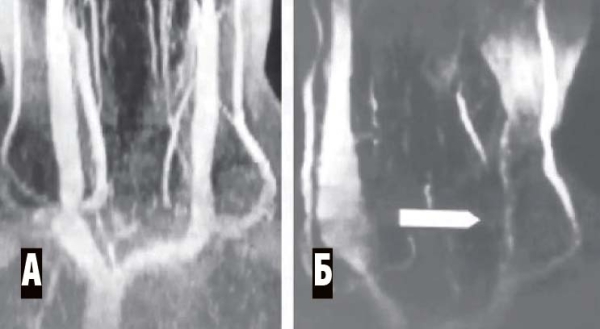

Магнитно-резонансная венография (аппараты МРТ имеют специальную программу для такого исследования). Исследуются синусы головного мозга, а также вены шеи. Всегда сравниваются правая и левая стороны (см. рис. 4, 5).

Рисунок 5. МР-венография при тромбозе синусов. А — левая сторона, обнаружено отсутствие сигнала от левых поперечного и сигмовидного синусов (признак тромбоза). Б — правая сторона, кровоток по синусам в норме.

МР-венография брахиоцефальных вен (см. рис. 6).

Рисунок 6. МР-венограмма. Мышечная компрессия внутренней яремной вены. А — брахиоцефальные вены в норме, Б — сдавление левой внутренней яремной вены гипертрофированными нижними шейными мышцами (уровень сдавления показан стрелкой). Противоположная внутренняя яремная вена компенсаторно расширена.